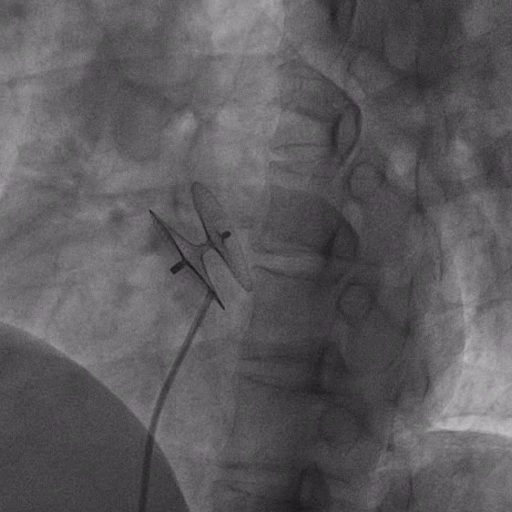

在獲得患者同意后,1月12日,尚福軍主任為患者進(jìn)行了PFO封堵術(shù)。術(shù)中造影可見封堵器殘余漏,尚福軍主任用精湛的技藝,順利通過(guò)封堵器殘余漏裂縫,將右心導(dǎo)管從右房送入左房,且順利到達(dá)肺靜脈;遂行卵圓孔未閉封堵術(shù)后殘余漏再次封堵;且完美釋放PFO封堵器,可見兩封堵器呈“馬蹄蓮”狀,再次術(shù)中造影未見殘余漏。